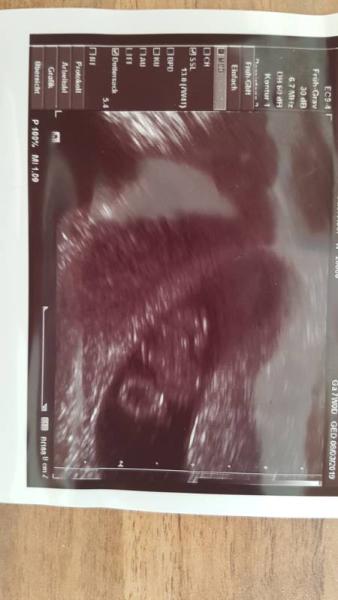

Hallöchen bin neu hier , Bin 30 Jahre und ist meine 2 Schwangerschaft .War heute bei Frauenarzt letztes mal in der 4 SSW gewesen weil oft Bauchschmerzen hatte da war noch nicht viel zu sehen . Heute ist soweit alles da wie es sein sollte und herzl hat auch geschlagen hat sich auch ordendlich bewegt. Und ich bin nun auch etwas beruhigter .

Bild zu 7SSW - Forum für März - Mamis